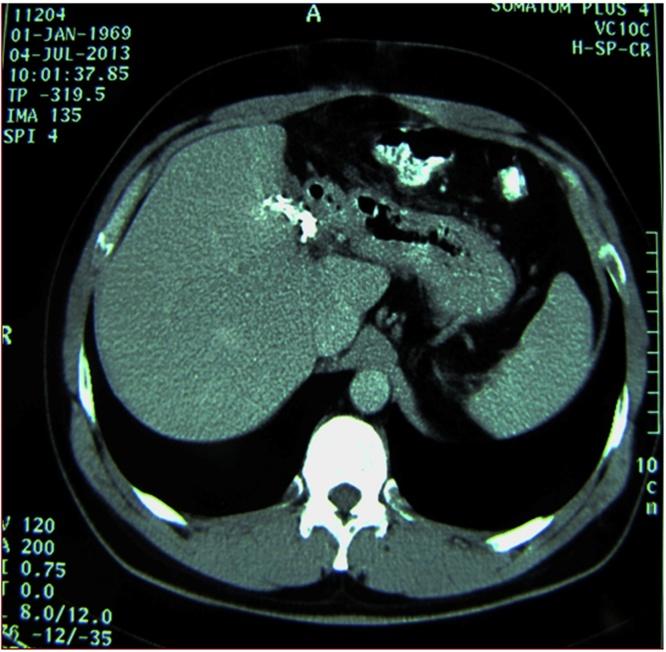

We report two cases of huge (25cm and 20cm in diameter, respectively) echinococcal cysts located in the left liver, which presented as a large palpable mass causing compression symptoms. Diagnosis was established with CT scan showing a cystic mass with the characteristic daughter cysts and reactive layer (pericystic wall) consisting of fibrous connective tissue and calcifications. Both patients were treated radically with left hepatectomy and had uneventful postoperative course and no recurrence upon follow-up.

我们报告两例位于肝脏左叶的巨大棘球蚴囊肿(直径分别为25厘米和20厘米),表现为可触及的巨大肿块并引起压迫症状。通过CT扫描确诊,显示为囊性肿块,具有特征性的子囊和由纤维结缔组织及钙化构成的反应层(包囊壁)。两名患者均接受了左半肝切除术根治性治疗,术后恢复顺利,随访无复发。